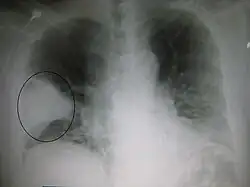

- Right upper lobe pneumonia as marked by the circle.